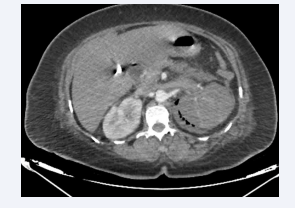

Axial section of an abdominal CT scan without intravenous  contrast injection showing air bubbles in the parenchyma and  excretory tracts of the right kidney and in the excretory and perirenal  tracts of the left kidney. The appearance is compatible with bilateral  EPN, class 4 according to Huang et al.

Figure 2: Axial section of an abdominal CT scan without intravenous contrast injection showing air bubbles in the parenchyma and excretory tracts of the right kidney and in the excretory and perirenal tracts of the left kidney. The appearance is compatible with bilateral EPN, class 4 according to Huang et al.